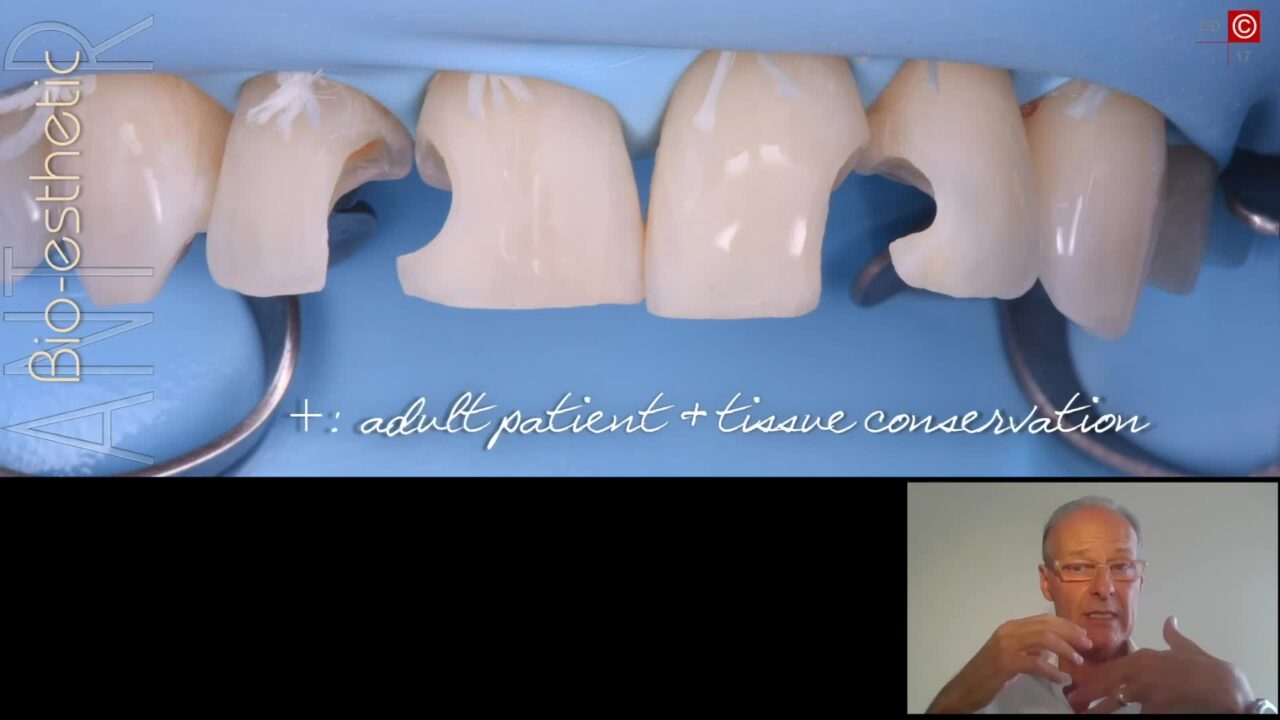

Dr. Egon Euwe

Dr. Egon Euwe

The Biologic Prosthetic Interface in Modern Esthetic Implantology – Revealing the Hidden Secrets of the Transgingival Part